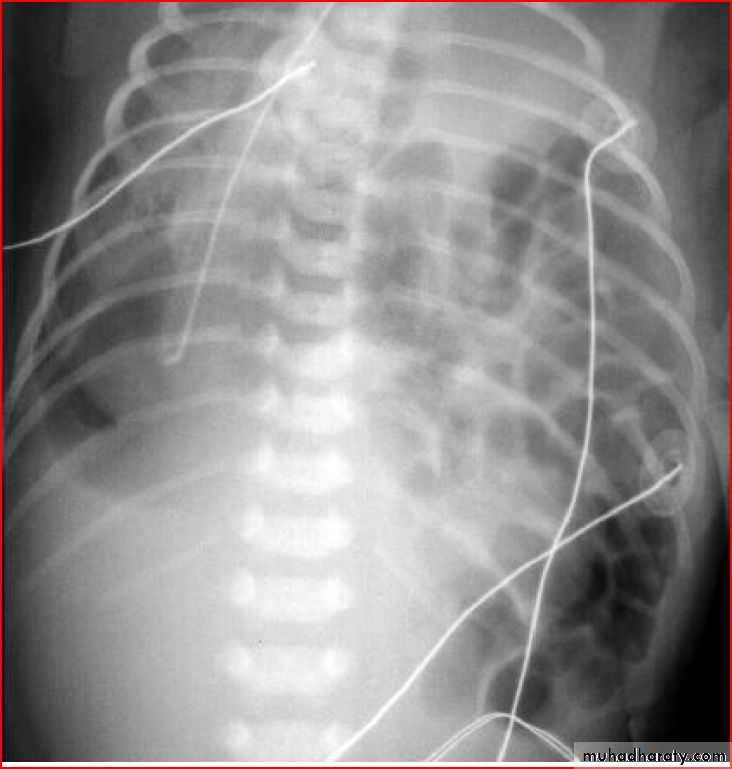

Tention pneumothorax ( shifting mediastinum )

Endotracheal tubeSo, +ve pressure ventilation complicated to pneumothorax

Rt. Total lung collapse

RDS with pneumomediastinum as rds complication